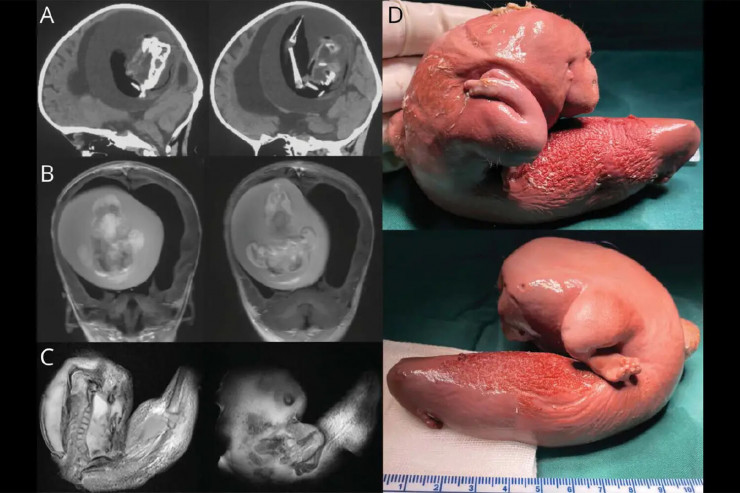

Плод длиной около 10 сантиметров обнаружили в мозге девочки, когда родители отвезли ее в больницу из-за увеличения черепа и проблем с моторикой.

Врачи отметили, что у плода развились верхние конечности, кости и даже ногти. Это означает, что он, вероятно, продолжал расти в течение нескольких месяцев в теле сестры. Это было возможно, так как кровеносная система плода была соединена с системой кровообращения девочки.

Фото: Wolters Kluwer Health, Inc.

"Плод в плоде" - это медицинский термин, обозначающий редкое явление, при котором близнецы сливаются в утробе матери и один из них физически развивается внутри другого. Задокументировано всего около 200 случаев "плода в плоде". Их находили в области таза, рта, кишечника и даже мошонки. Случаев, связанных с черепом, насчитывается всего 18. Обычно их находили у младенцев, но несколько случаев были зарегистрированы среди взрослых. После операции по удалению больные обычно полностью выздоравливают.